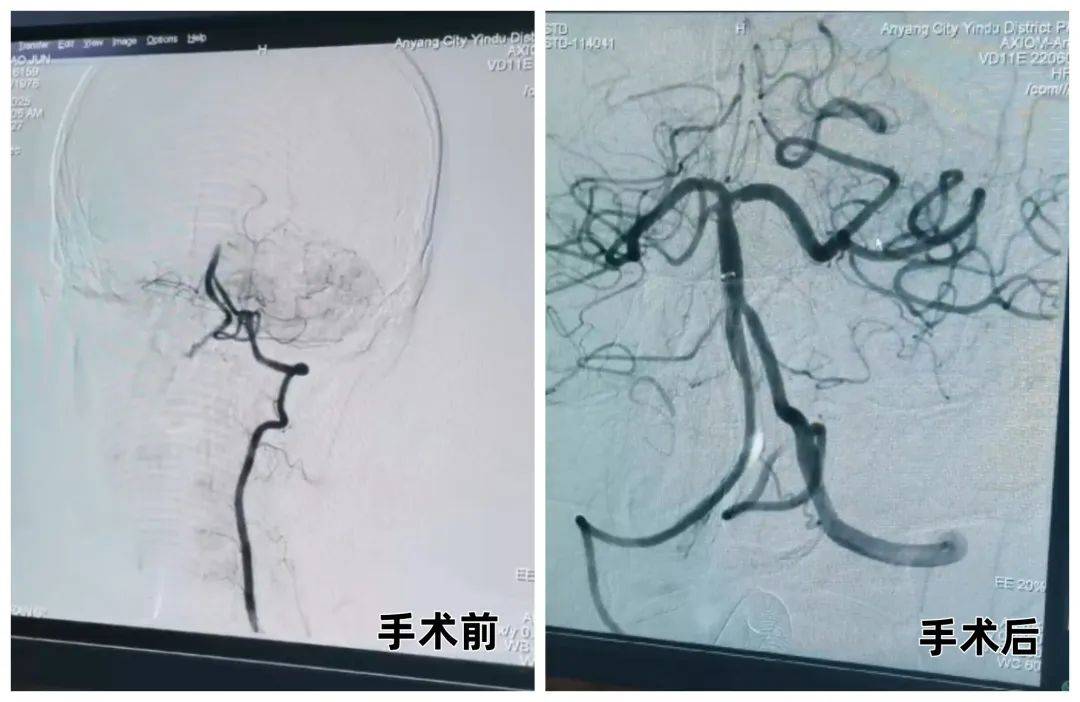

70 歲的武大娘晨起突發(fā)右側(cè)肢體無力,急診120送達殷都區(qū)人民醫(yī)院時已無法行走。神經(jīng)內(nèi)科綠色通道醫(yī)師張偉艷在39分鐘內(nèi)完成評估,確診急性腦梗死并啟動靜脈溶栓治療。然而,溶栓后15分鐘患者癥狀加重,出現(xiàn)意識障礙。介入醫(yī)師梁麗平、張曉亭緊急評估后,決定實施急診取栓術(shù)。在癥狀加重 1小時后,手術(shù)團隊于全麻下成功完成顱內(nèi)取栓。10余天后,武大娘在家人陪同下康復出院,重新回歸平靜生活。